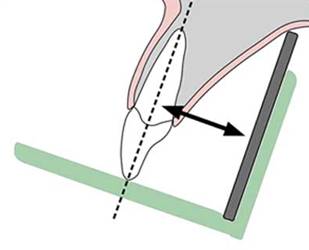

Técnica

paralela para la toma radiográfica periapical ó

del cono largo:

-

El diente

debe estar tan paralelo y cercano a la

película como sea posible, y

-

La fuente

de los Rayos X debe ser pequeña y estar tan

lejos del diente como sea posible.

|